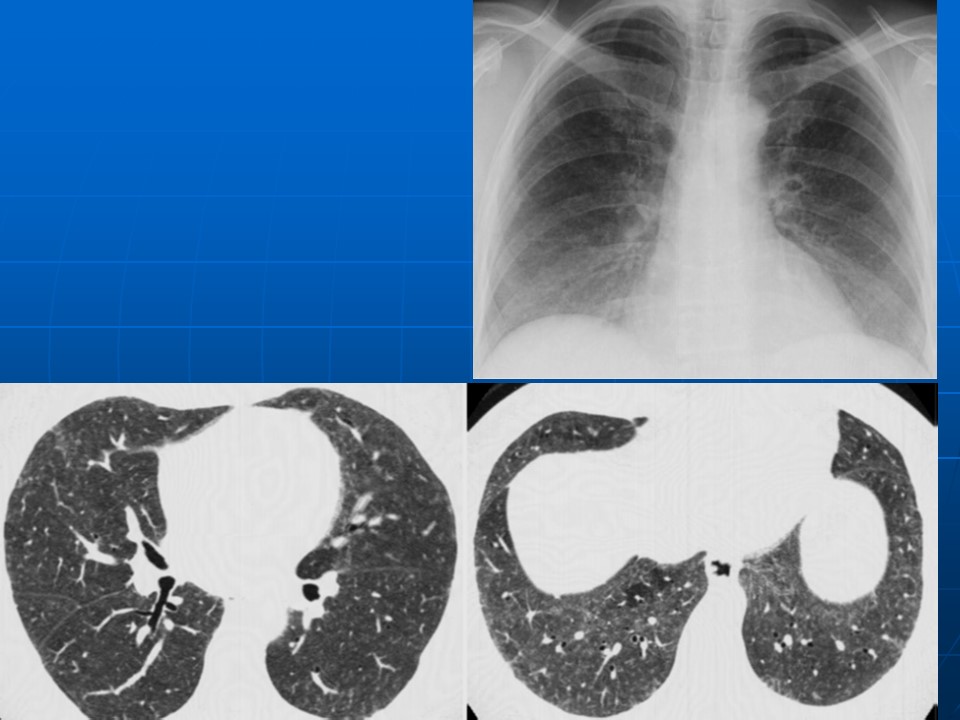

HRCT树芽征的诊断价值